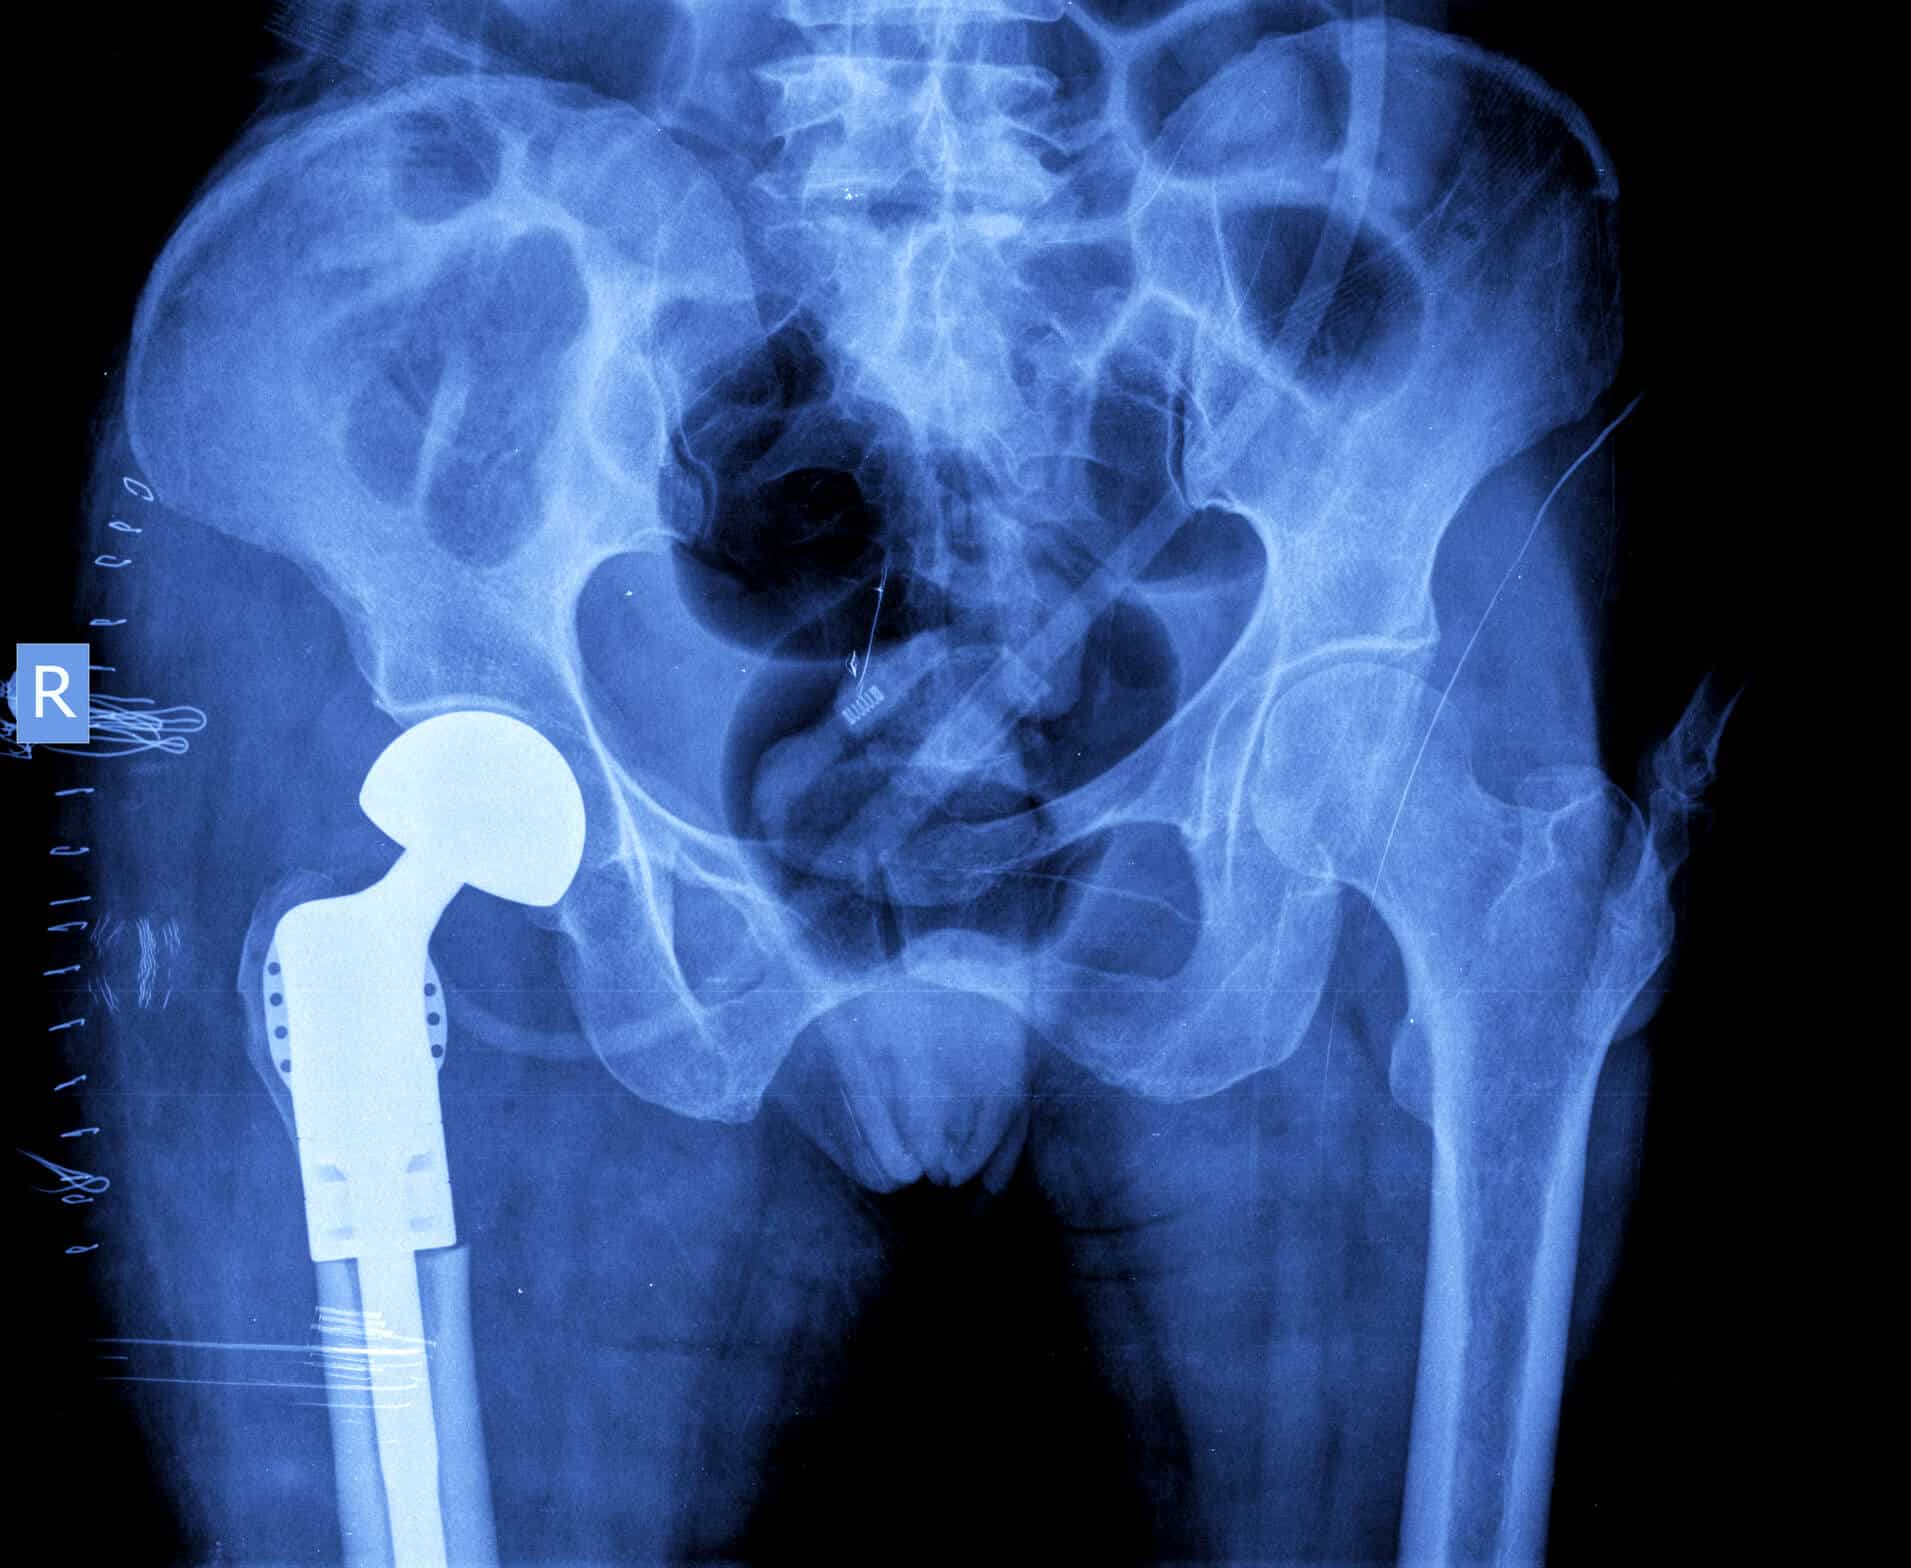

All hip replacements contain several different parts, often including an acetabular liner. When a person’s hip is replaced, typically a metal cup is inserted into the hip socket (acetabulum), often anchored with screws.

An acetabular liner, typically made of some form of plastic or ceramic, is often inserted into this acetabular cup. A femoral head component — a spherical piece of metal intended to replicate the top or “ball” of a person’s femur bone — sits against the acetabular liner.

These physicians reviewed patient data from January 2009 to June 2019 for all patients who had revision surgery after being implanted with the Exactech Connexion GXL acetabular liners at their institution. These orthopedic surgeons found that all of the patients who had to have a revision surgery, or revision surgery had been recommended, after being implanted with an Exactech Connexion GXL acetabular liner demonstrated radiographic osteolysis around the liners. This means X-rays of their hips showed bone loss and destruction to the hip socket (acetabulum). (3)